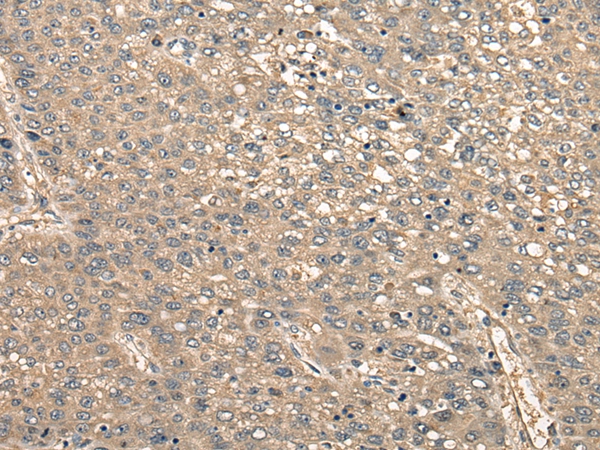

The image on the left is immunohistochemistry of paraffin-embedded Human liver cancer tissue using 46414(CCDC102A Antibody) at dilution 1/30, on the right is treated with synthetic peptide. (Original magnification: x200)